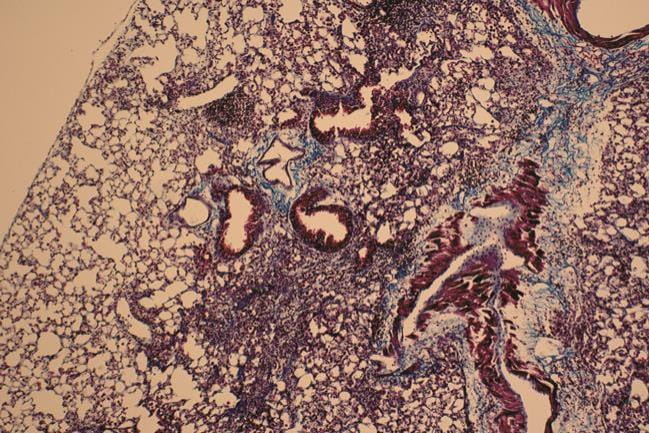

Fibrotic lung tissue isolated from mice that received bleomycin

When given by intratracheal injection, bleomycin causes fibrotic changes in the lungs, including peribronchial and interstitial infiltration of inflammatory cells, thickening of alveolar walls, and the development of fibrotic lesions with excess deposition of extracellular matrix protein. The MUSC investigators used this bleomycin-induced model of lung fibrosis to evaluate the anti-fibrotic effects of M10. As expected, mice receiving bleomycin plus a scrambled peptide showed greater than eight times more lung fibrosis than controls receiving saline and scrambled peptide, but that fibrosis was reversed when mice were administered both bleomycin and M10, suggesting the anti-fibrotic potential of M10.